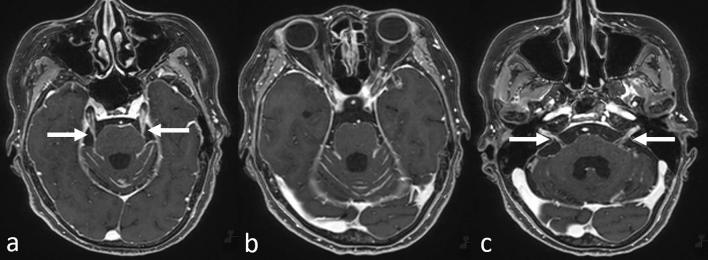

Although metastases found during head magnetic resonance imaging (MRI) are not limited to metastatic brain tumors, the MRI is a very common method for "brain metastasis screening," a modality that is being increasingly performed. In this review, we describe MRI findings of nonbrain metastases and discuss ways to avoid missing these lesions. Metastatic cranial bone tumors are among the most common nonbrain metastatic lesions found on head MRI, followed by leptomeningeal carcinomatosis. The other less-frequent metastatic lesions include those in the ventricle/choroid plexus, the pituitary gland and stalk, and the pineal gland. Metastases in the head and neck area, as well as cranial and intracranial lesions, should be carefully evaluated. Furthermore, direct geographical invasion, perineural spread, and double cancers should also be considered. While it is important to recognize these metastatic lesions on MRI, because they may necessitate a change in treatment strategy that could lead to an improvement in prognosis due to early introduction of therapy, nonbrain lesions should also be given greater attention, given the increasing survival of patients with cancer and advances in MRI technology, such as contrast-enhanced-3D T1-weighted imaging.

尽管头部磁共振成像(MRI)检查发现的转移不限于脑转移瘤,但 MRI 是一种非常常见的“脑转移筛查”方法,这种方法的应用越来越广泛。在这篇综述中,我们描述了非脑部转移瘤的 MRI 表现,并讨论了避免遗漏这些病变的方法。转移性颅骨肿瘤是头部 MRI 上最常见的非脑转移病变之一,其次是软脑膜癌病。其他较少见的转移性病变包括脑室/脉络丛、垂体及其柄和松果体转移瘤。头颈部、颅腔和颅内病变应仔细评估。此外,还应考虑直接的地理侵犯、神经周围扩散和双癌。虽然在 MRI 上识别这些转移瘤很重要,因为它们可能需要改变治疗策略,通过早期引入治疗来改善预后,但鉴于癌症患者的生存率提高和 MRI 技术的进步,如增强-3D T1 加权成像,也应更加关注非脑部病变。